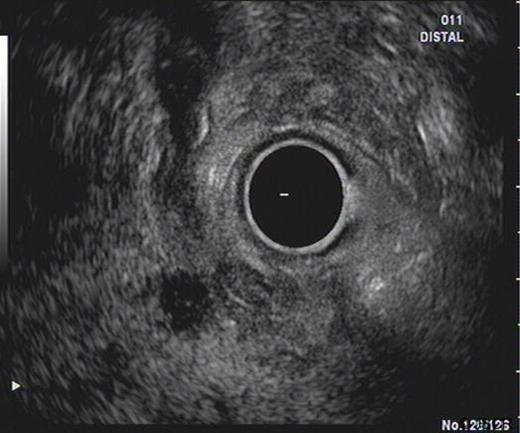

SC was a 46 yr old gentleman who was referred from his district hospital with a six month history of upper abdominal pain and weight loss. His past medical history included a prolapsed lumbar disc and he was not on any regular medications. A family history revealed that his grandfather had gastric cancer. He was a non-smoker and had a moderate alcohol intake. A Computer Tomography (CT) scan of his abdomen and pelvis revealed no significant abnormalities except for changes suspicious of duodenal diverticular disease. Prior to his consultation he had endoscopies of both his upper and lower gastro-intestinal tracts which were reported as revealing no abnormalities. An Endoscopic Retrograde Cholangio-Pancreatogram (ERCP) was precluded due to the difficulty of the duodenal diverticulum obscuring the ampulla of Vater. A subsequent Endoscopic Ultrasound Scan (EUS) revealed an 8mm soft tissue lesion in the distal common bile duct (CBD) causing dilatation of the pancreatic duct (Figure 1). Elastography showed this to be a firm mass. FNA sample were subsequently taken from the mass which revealed no malignant cells. The HPB MDT meeting felt that although the lesion could be benign, a malignant process could not be excluded thus a Whipple’s procedure was advised.

EUS demonstrating lesion at the pancreatic head with thickening of distal CBD